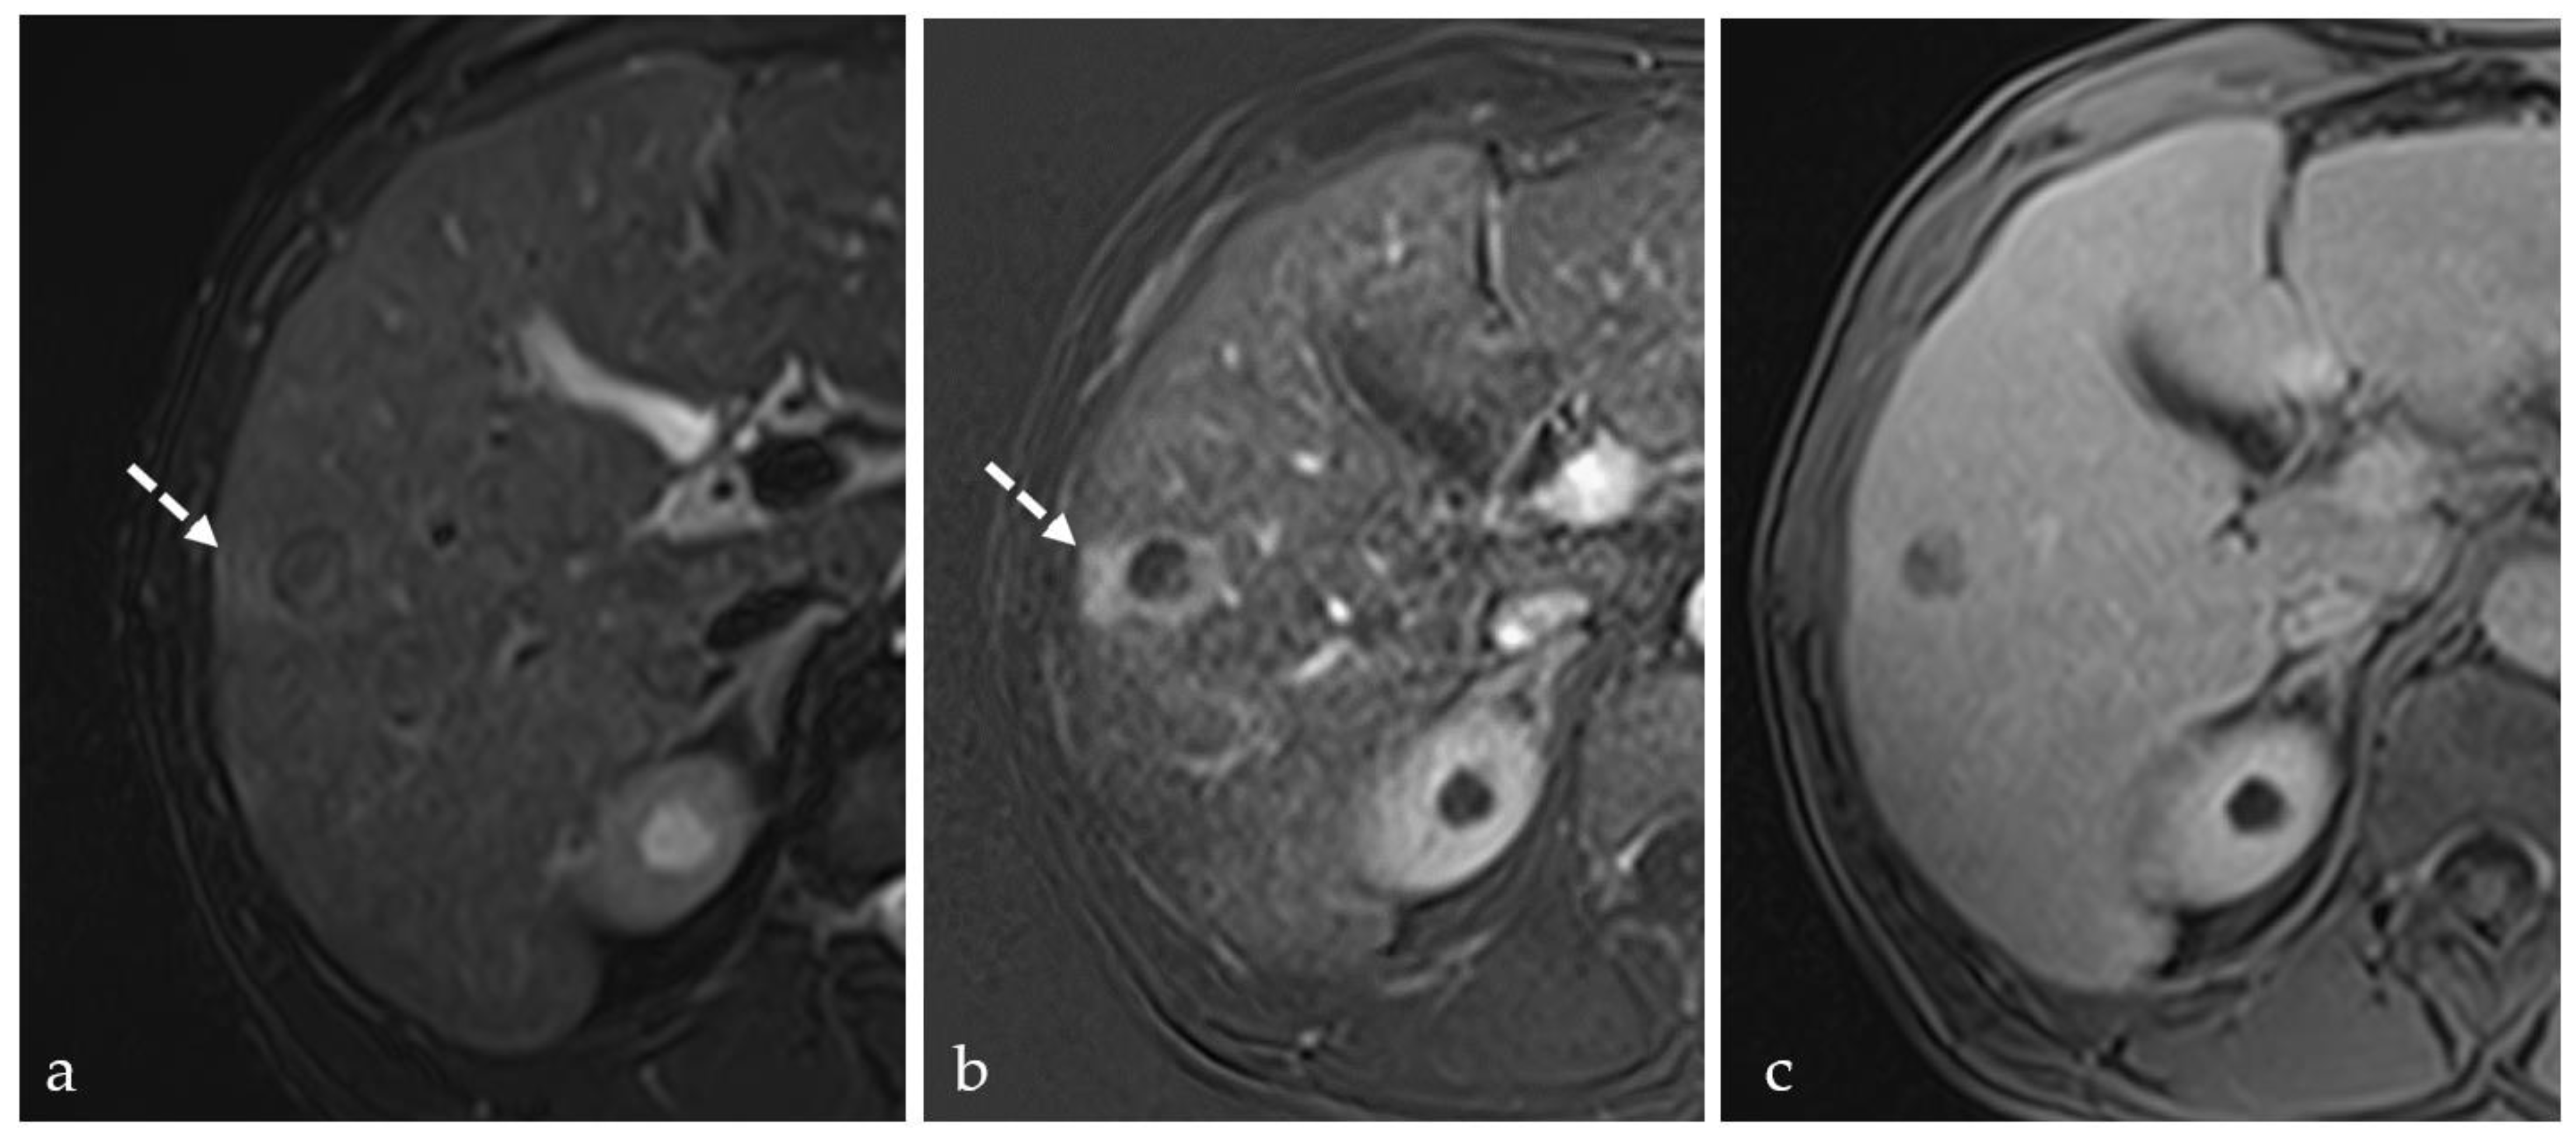

3.3. Transient Hyperemia

3.5. Post-Treatment Imaging Features of Tumor Viability